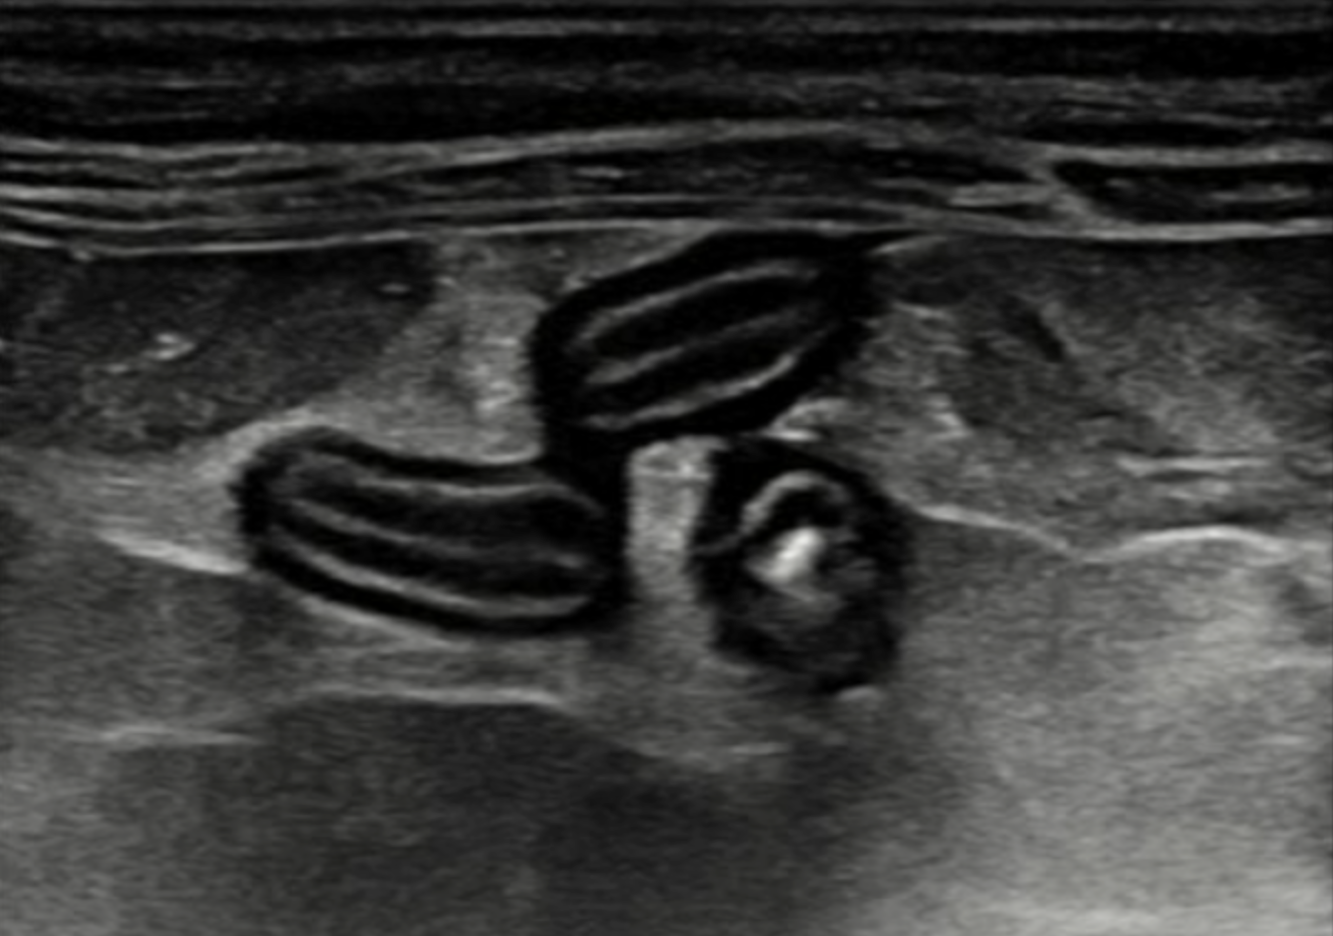

JVI is an independently owned small animal diagnostic imaging service. We offer mobile ultrasound by a board-certified veterinary radiologist to small animal practices in parts of San Mateo County.

Our goal is to provide high quality exams and reports to help veterinarians make informed clinical decisions for their patients while maintaining an efficient workflow.